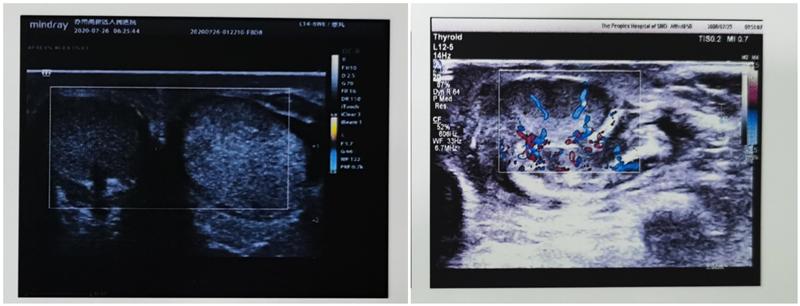

最近一段时间,苏州高新区人民医院泌尿外科一周内连续接诊了两例*丸睾**扭转患者。11岁的瑞瑞,凌晨三点左右突然被左侧“蛋疼”痛醒,坚强的他怕打搅到爸爸妈妈休息,坚持了两个小时没有吭声,最后实在是坚持不住了,并且出现了呕吐,才被父母发觉并送到我院就诊。医生通过彩色超声检查,发现其左侧*丸睾**血供消失,考虑左*丸睾**精索扭转,泌尿外科医生急诊进行了手术探查,术中发现瑞瑞的左侧*丸睾**扭转了360度,精索已经扭得像麻花,医生对他的*丸睾**精索进行了复位,幸运的是,瑞瑞来医院还算及时,从发病到手术不到5个小时,*丸睾**逐渐恢复血供,成功将这侧*丸睾**保存了下来。另一例患者,30多岁的李先生,在进行健身锻炼时,因为体位突然发生变化,出现了一侧*丸睾**剧烈疼痛,急诊来我院就诊。彩超检查发现疼痛一侧的*丸睾**内血流明显较对侧减少,急诊手术探查,发现*丸睾**已经扭转,及时进行了*丸睾**复位固定,手术后,*丸睾**血供恢复良好。

*丸睾**扭转可发生于任何年龄阶段,最常见于青少年(12~18 岁),约占85%,且以左侧为多见。这可能与左侧精索稍长于右侧有关。典型症状为突然发生的单侧*丸睾**剧烈疼痛,往往在剧烈运动后、夜间睡眠或者刚起床时,患侧*丸睾**附睾肿大,随着病情发展,阴囊可出现红肿或色泽改变,多数伴有恶心呕吐,少数有低热。*丸睾**扭转的程度和发病持续时间与*丸睾**血液循环障碍以及病理生理改变的严重程度密切相关,彩色超声血流图是最具有诊断价值的影像学检查,可以详细、实时地观察*丸睾**内的血流情况及其变化,目前被广泛应用于*丸睾**扭转的诊断和鉴别诊断。*丸睾**内动脉血流信号明显减少或消失是诊断本病的最可靠标准。